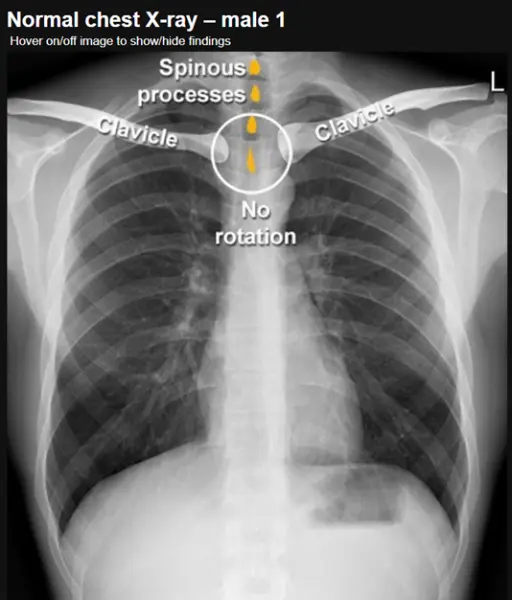

- Độ xoay (Rotation): mấu gai đốt sống nằm giữa 2 đầu trong xương đòn

Bệnh nhân nam, không bị xoay – các mỏm gai của đốt sống ngực nằm chính giữa, giữa các đầu trong của xương đòn